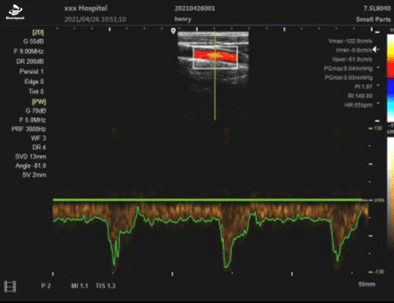

PW模式

| 显示模式 | B、 B/B、4B、B+M、CFM、B+CFM、PDI、B+PDI、PW |

| 应用方式 | 妇产科、小器官、泌尿科、儿科、心脏等 |